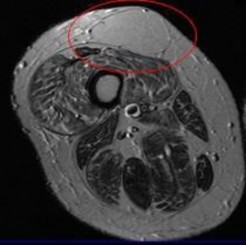

A 15-year-old male presents with deep knee pain awakening him at night. Radiographs show a permeative destructive lesion in the distal femoral metaphysis with a 'sunburst' periosteal reaction and Codman's triangle.

Biopsy confirms high-grade conventional osteosarcoma. What is the most critical prognostic factor for long-term overall survival in this patient?

Explanation

For localized high-grade osteosarcoma, the most important prognostic indicator is the histologic response to neoadjuvant chemotherapy. This is evaluated during the definitive resection. A 'good response' is typically defined as greater than 90% or 99% tumor necrosis. Patients who achieve this level of necrosis have a significantly improved disease-free and overall survival rate compared to 'poor responders' who have extensive viable tumor cells remaining.